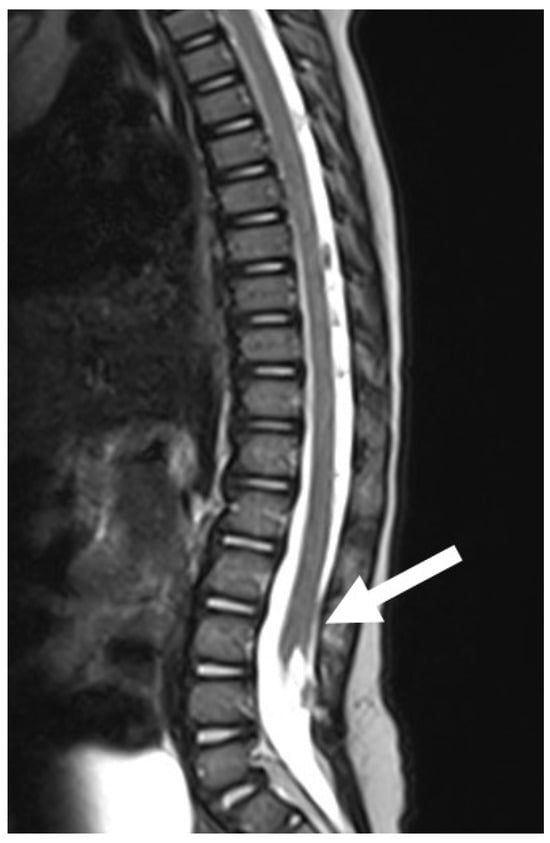

Figure 5. A preoperative (A) scan of a SCM1 with a bone spur separating two dural sacs and two hemicords (white arrow). The postoperative image (B) shows the removal of the bone spur and the reconstruction of a single dural sac.

SCM is characterised by a split, double spinal cord. It is caused by a defect in the phase of cellular migration from the epiblast to the primitive cord, a process that normally leads to cellular integration and the formation of the notochord. If integration does not occur, two notochords are formed, triggering the formation of two hemicords [4]. A distinction is made between SCM1, in which there is a bone spur between the two halves of the spinal cord, and SCM2, in which the two hemicords are separated by a fibrous membrane. SCM1 is characterised by two dural sacs, while the dural sac in SCM2 is a single one. Both forms hinder the normal ascent of the conus and the spinal cord. For this reason, it is necessary to remove the bone or membrane separating the two hemicords and create a single dural sac. In our series, SCM1 was present in three cases and SCM2 in two cases. Two patients with SCM1 were treated surgically (Figure 5), and one patient with SCM1 rejected surgical treatment. Both patients with SCM2 are asymptomatic and are under strict follow-up with annual electromyographic and urodynamic tests.